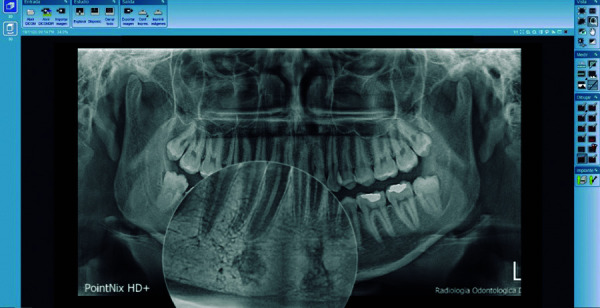

Objective: The objective of this study was to determine, describe and identify the prevalence of radiopaque images compatible with idiopathic osteosclerosis in digital panoramic radiographs taken in patients between the ages of 18 and 50.

Materials and methods: The study design was descriptive, cross-sectional and retrospective. The sample consisted of 500 digital panoramic radiographs taken between January 1, 2016 and December 31, 2018, in the target population aged between 18 and 50 years from Ayacucho - Peru, attended at a private radiological center. The radiographs obtained were analyzed using the Romexis viewer version 5.3 program, and the results were recorded on a data collection sheet. The Chi-square test was used to establish associations among the variables evaluated. A P <0.05 was considered significant.

Results: 500 digital panoramic radiographs were analyzed, showing a prevalence of idiopathic osteosclerosis of 17.4%, of which 12% were female and 5.4% male, and according to age, the presence of idiopathic osteosclerosis was more prevalent in the second decade of life.